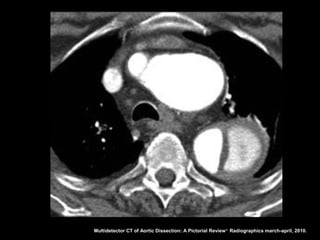

Dissecção aórtica

Angiotomografia

Diagnóstico: identificação do flap intimal, que se

apresenta como uma fina membrana separando a

luz falsa da verdadeira;

Sensibilidade e especifidade acima de 95% na

detecção do flap intimal;

Após diagnóstico: localizar, definir envolvimento de

ramos aórticos e identificar fatores agravantes

relacionados à própria aorta.

Multidetector CT of Aortic Dissection: A Pictorial Review 1. Radiographics march-april, 2010.